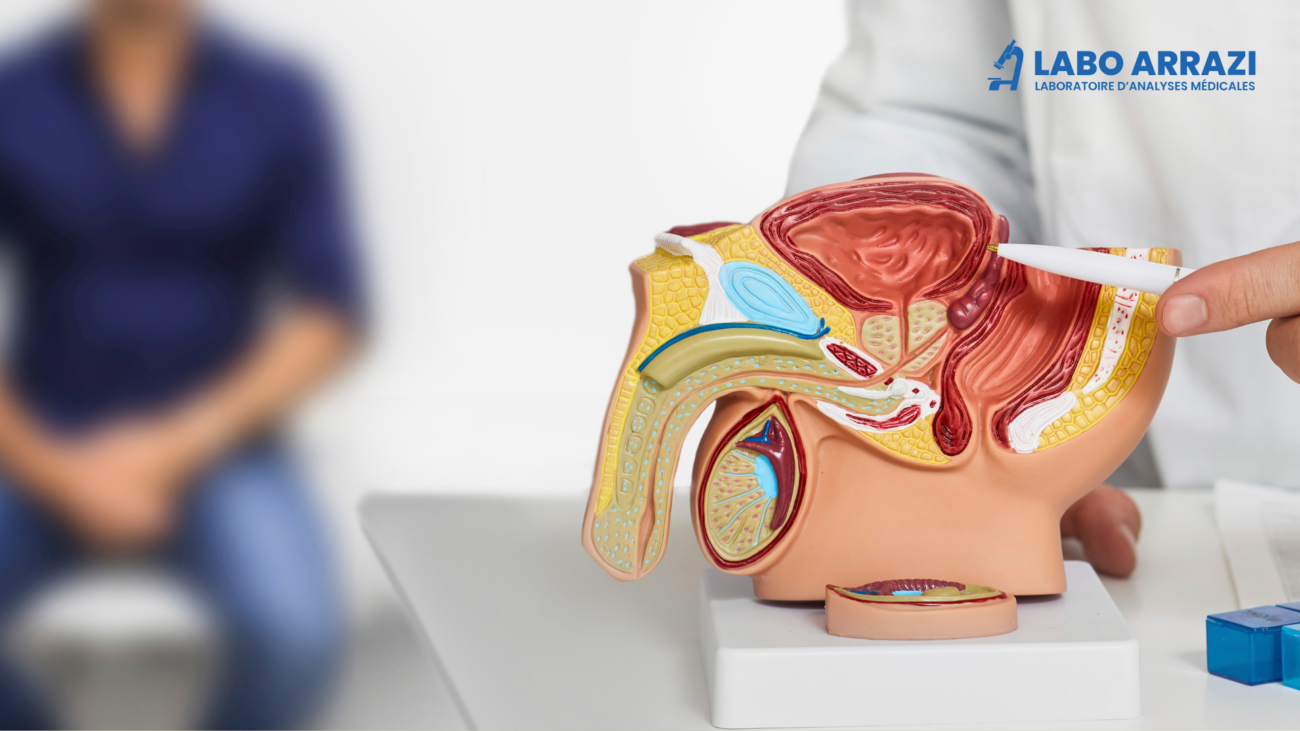

Un examen clé pour évaluer la santé de la prostate

Qu’est-ce que le Dosage du PSA ?

Le Dosage du PSA (Antigène Prostatique Spécifique) est un examen sanguin qui permet de mesurer le taux de PSA dans le sang. Le PSA est une protéine produite par la prostate, et son dosage est principalement utilisé pour le dépistage, le suivi et l’évaluation des maladies de la prostate, notamment l’hyperplasie bénigne de la prostate, la prostatite et le cancer de la prostate.